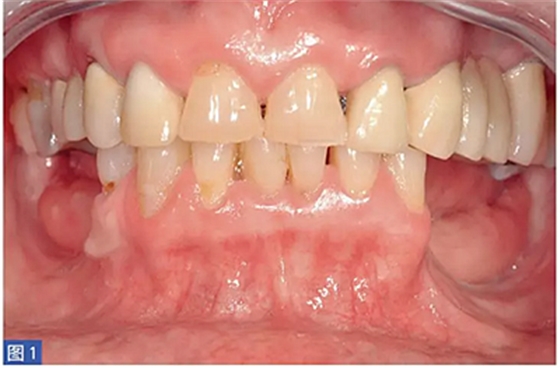

在整個(gè)手術(shù)過(guò)程中以及術(shù)后12 個(gè)月都要評(píng)估并發(fā)癥的發(fā)生。在術(shù)后12 個(gè)月,患者都要通過(guò)視覺(jué)模擬量表(VAS)對(duì)手術(shù)的滿意度從0(非常不滿意)到10(非常滿意)進(jìn)行評(píng)估。這些問(wèn)題針對(duì)對(duì)于治療過(guò)程的主觀評(píng)價(jià)。圖1-12 顯示了兩個(gè)典型病例的手術(shù)。

圖1:病例1. 術(shù)前照,59 歲非吸煙者女性,左下頜牙槽嵴重度萎縮。